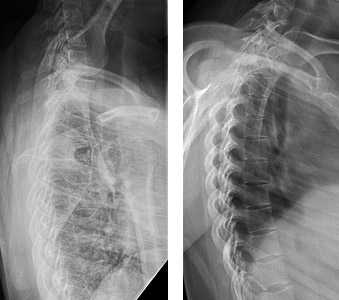

Left: Lateral thoracic with no breathing technique; Right: Lateral thoracic with breathing technique.

All of these techniques can be greatly improved with the use of a breathing technique. (Figure 1A and 1B) Remember that an exposure time of 1 second or greater is required to achieve sufficient blurring of the thoracic soft tissues. You will have to adjust the technical factors accordingly.